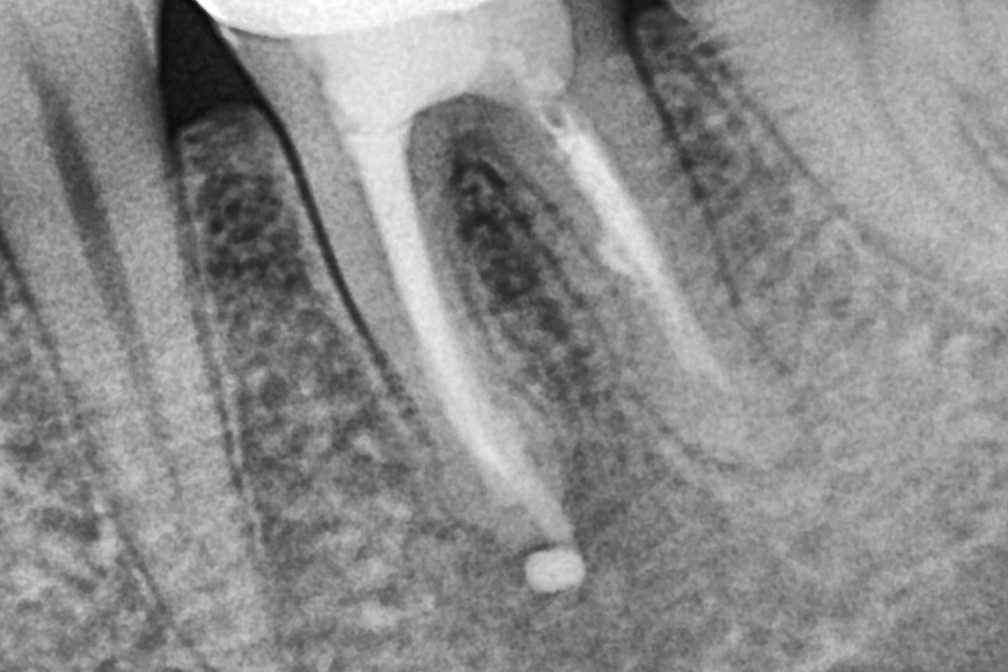

After 2025년 12월 23일

위 전후사진은 이미지사진으로 실제 눈으로 보는 것과는 다를 수 있으며, 환자의 치아상태과 방법에 따라 치료결과가 다를수 있습니다.

사진의 날짜는 촬영날짜이며 치료의 기간이 아님을 알려드립니다.

치료 후 치아표면의 탈회 , 충치, 치근흡수 등의 부작용이 있을 수 있습니다.